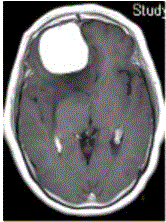

问题 女,64岁,发作性意识丧失,左侧肢体无力,MR显示右侧额叶等T1信号影(下图),病变明显强化,最可能的诊断是

选项 A.室管膜瘤 B.星形细胞瘤 C.脊索瘤 D.脑膜瘤 E.转移瘤

答案 D